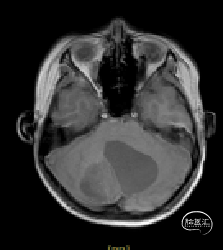

术前MRI

小脑肿瘤(毛细胞型星形细胞瘤?)

枕下后正中开颅小脑肿瘤切除术